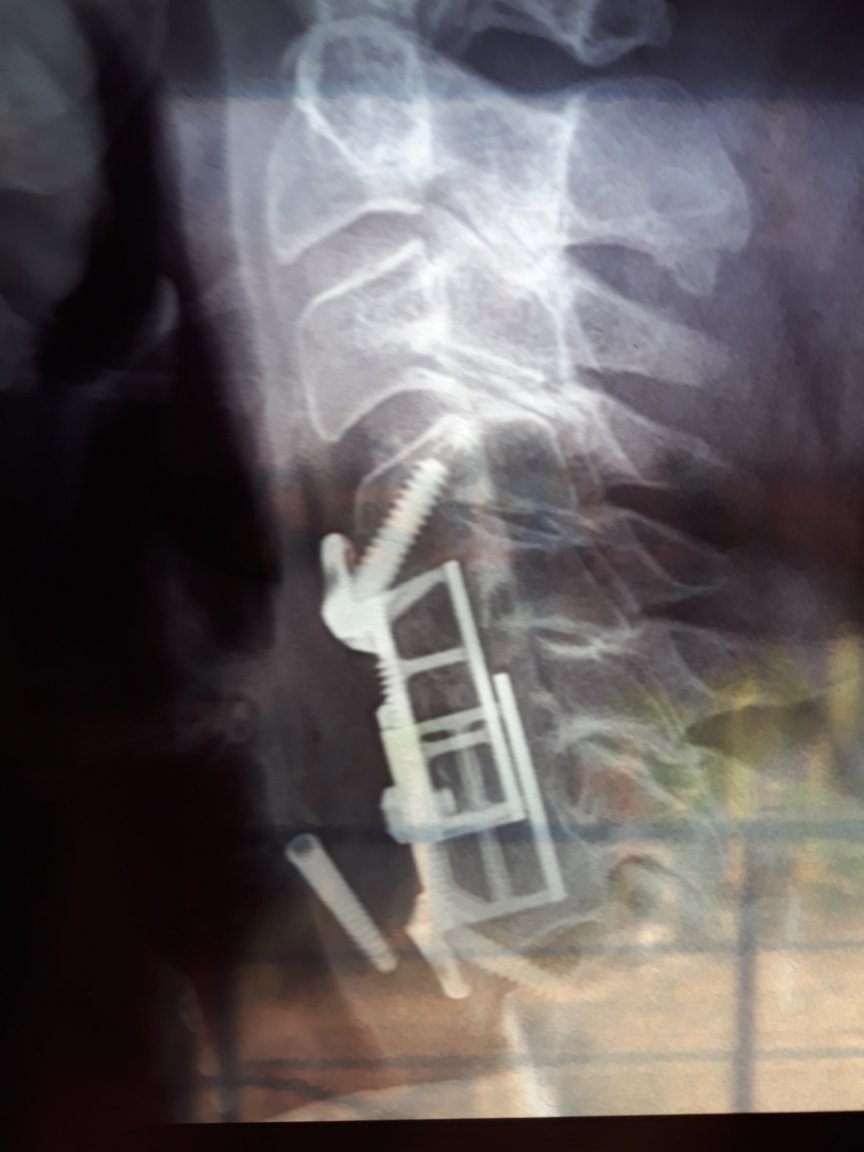

Here is my setup and my neck xray. As you can see my pc is my tv and my tv is my monitor. If that makes sense at all. I thank everybody for the advice except the porn man 😉 I'll keep the mouse closer and will go back to trackball mouse. I do exercises but not really works. The elbow thing is also a option. Thanks again guys and girls- Neck and shoulder pains from computer mouse

That's because only my neck hurts. Because my nerv system is compromised my muscles will act up and (don't know how to say in English) it looks like I do heavy work all the time so then I get the muscle pains going from shoulder blades up to my ear (left side only.- Neck and shoulder pains from computer mouse

I have tried the normal, trackball and now a so called ergometric shaped form of mouse but I still get terrible pains. It does not help that part of my neck's discs are titanium implants. So I was wondering if their are other forms of mouse one can try.- Which members do you think are Russian/Chinese/NK etc bots?